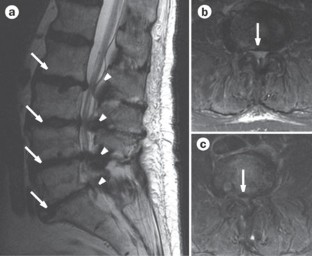

Kobayashi, S. et al. Imaging of cauda equina edema in lumbar canal stenosis by using gadolinium-enhanced MR imaging: experimental constriction injury. AJNR Am. J. Neuroradiol. 27, 346–353 (2006).